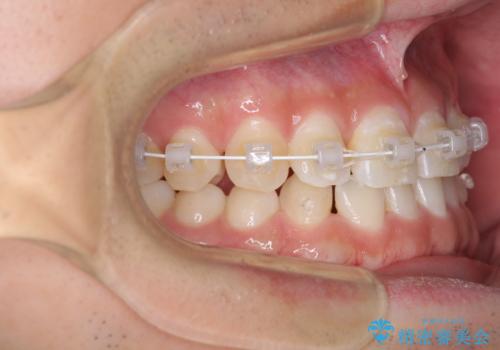

- 矯正装置

- 審美装置

- 1年1ヶ月

- 10-30回

下顎臼歯にインプラント補綴治療がされており、全顎治療するにはクラウンの作り替えが必要となる旨を説明し、ワイヤー装置により上顎のみの矯正治療を行うこととしました。

空隙歯列弓はマウスピースによる保定を行っても、すぐに後戻りを起こしてしまうため、ワイヤーリテーナーによる保定を併用することとしました。